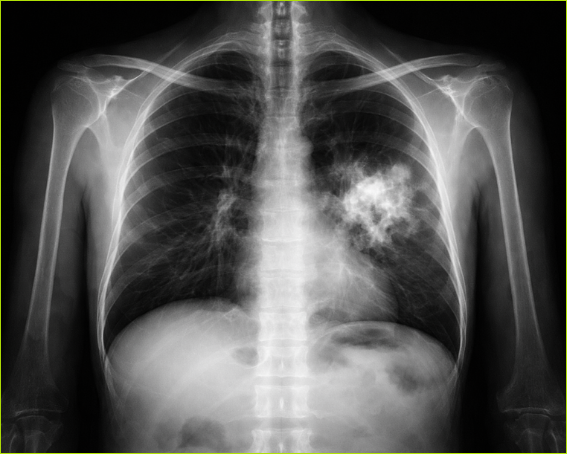

Rak płuca przez lata opisywano językiem dobrze znanym pacjentom i lekarzom – mutacje, przerzuty, tomografia komputerowa, operacja, chemia, immunoterapia. To słownik walki z jedną z najpoważniejszych chorób współczesności. Ale obok tego tradycyjnego obrazu wyrasta dziś drugi, bardziej złożony. Guz nie jest już widziany wyłącznie jako masa komórek, które wymknęły się spod kontroli. Coraz częściej przedstawia się go jako biologiczne środowisko, z naczyniami krwionośnymi, komórkami odpornościowymi, stanem zapalnym, zaburzonym metabolizmem i siecią lokalnych zależności.

Nowotwór nie rośnie w pustce. Komórki raka wydzielają substancje chemiczne, wpływają na naczynia krwionośne, zmieniają lokalny odczyn pH, przyciągają lub wypierają komórki układu odpornościowego. Wokół guza tworzy się specyficzne mikrośrodowisko. To właśnie ono interesuje dziś onkologów równie mocno jak sam guz.

Bo często o przebiegu choroby decyduje nie tylko to, jakie mutacje doprowadziły do rozwoju nowotworu, lecz także to, jak wygląda jego otoczenie. Czy układ odpornościowy jest aktywny? Czy w tkance występuje przewlekły stan zapalny? Czy guz ma dobre ukrwienie? Czy reaguje na leczenie immunologiczne?